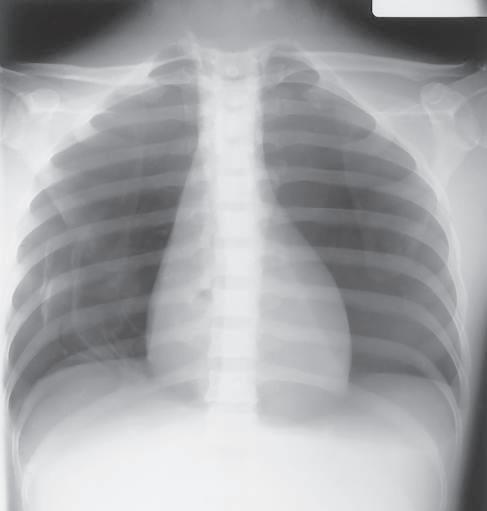

Definition Radiographic contrast is defined as the difference in density between adjacent areas of a radiographic image. When the density difference is large, the contrast is high and when the density difference is small, the contrast is low. This is demonstrated by the step wedge and by the chest radiograph in Fig. 1-126, which shows greater differences in density between adjacent areas; thus, this would be high contrast. Fig. 1-127 shows low contrast with less difference in density on adjacent areas of the step wedge and the associated radiograph.

Contrast can be described as long-scale or short-scale contrast, referring to the total range of optical densities from the lightest to the darkest part of the radiographic image. This is also demonstrated in Fig. 1-126, which shows short-scale/high-contrast (greater differences in adjacent densities and fewer visible density steps), compared with Fig. 1-127, which illustrates long-scale/ low-contrast.

Low or high contrast is not good or bad by itself. For example, low contrast (long-scale contrast) is desirable on radiographic images of the chest. Many shades of gray are required for visualization of fine lung markings, as is illustrated by the two chest radiographs in Figs. 1-126 and 1-127. The low-contrast (long-scale contrast) image in Fig. 1-127 reveals more shades of gray, as evident by the faint outlines of vertebrae that are visible through the heart and the mediastinal structures. The shades of gray that outline the vertebrae are less visible through the heart and the mediastinum on the high-contrast chest radiograph shown in Fig. 1-126.

Fig. 1-127 Low-contrast, long-scale 110 kV, 10 mAs.